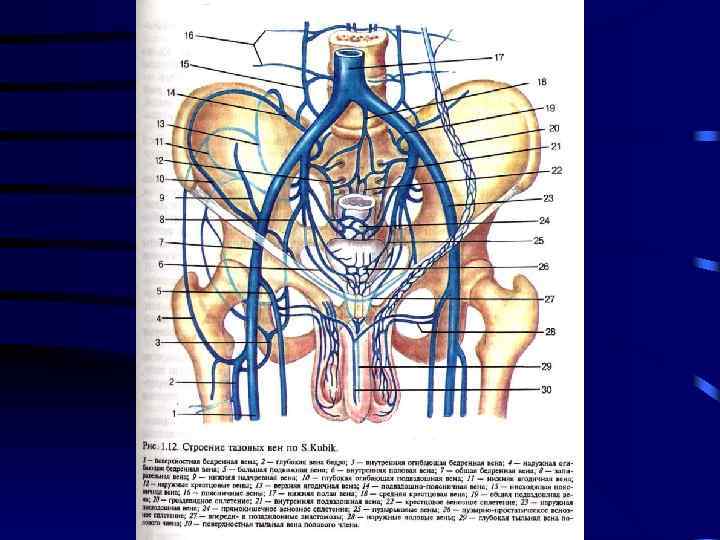

Острый тромбофлебит – острое воспаление венозной стенки с образованием тромба в просвете сосуда с нарушением оттока крови по вене. • По месту локализации различают: • • Тромбофлебит подкожных вен Тромбофлебит глубоких вен Тромбофлебит подвздошных вен Тромбофлебит подключичной вены – синдром Педжета-Шреттера

I. • Заболевания венозной системы Острые заболевания: 1) Острый тромбофлебит: a) b) c) 2) 3) • Поверхностных вен; Глубоких вен; Илеокавального сегмента Флебиты Флеботромбозы Хронические заболевания: 1) Варикозная болезнь: a) Первичная b) вторичная 2) Посттромбофлебитический синдром